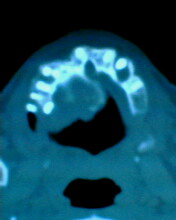

患者:男71岁,右侧上颚肿物无痛性生长7年.

右上颌骨近中线部见类圆形低密度区,上方见一液平,周围见一薄硬化环,前下方见一牙根,后方累及水平板。上方突入鼻腔前下部,下方突入口腔。

考虑:右侧上颌骨囊肿伴感染。